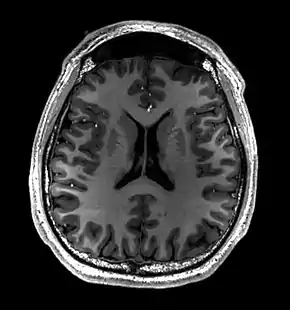

![]() Cross-sectional T1-weighted MRI of a healthy human brain acquired with an ultra high-field MR of 7 Tesla field strength | |

Magnetic resonance imaging of the brain uses magnetic resonance imaging (MRI) to produce high quality two-dimensional or three-dimensional images of the brain and brainstem as well as the cerebellum without the use of ionizing radiation (X-rays) or radioactive tracers.

- T1-weighted (T1W) images: Cerebrospinal fluid is dark. T1-weighted images are useful for visualizing normal anatomy.